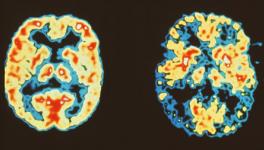

The data for the analyses were taken from clinical as well as autopsy reports on patients who succumbed to Alzheimer’s between 2005 and 2015. The confirmation of Alzheimer’s in the considered dataset was done on the basis of traditional abnormalities observed in brain autopsy (Autopsy is a detailed dissection of an organ of a deceased person and is done for determining the exact cause of the death) specimens.

These also included the presence of abnormal aggregation of proteins. It is well known that dementia patients, especially in Alzheimer’s disease, have an abnormal aggregation of a particular protein named beta amyloid, which has not been fully understood yet despite extensive research. In the study group, life expectancy ranged from one month to 130 months after the diagnosis of Alzheimer’s—most of the individuals in the study group were diagnosed on their first visit.